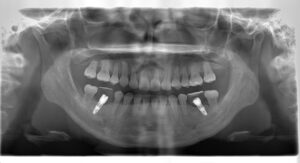

(治療後:写真右)

上下の歯の真ん中がお顔の中心と一致しました。

下顎両側の臼歯が欠損している部位には、矯正治療後にインプラントを埋入し、しっかりと上下の歯が咬み合うようになりました。